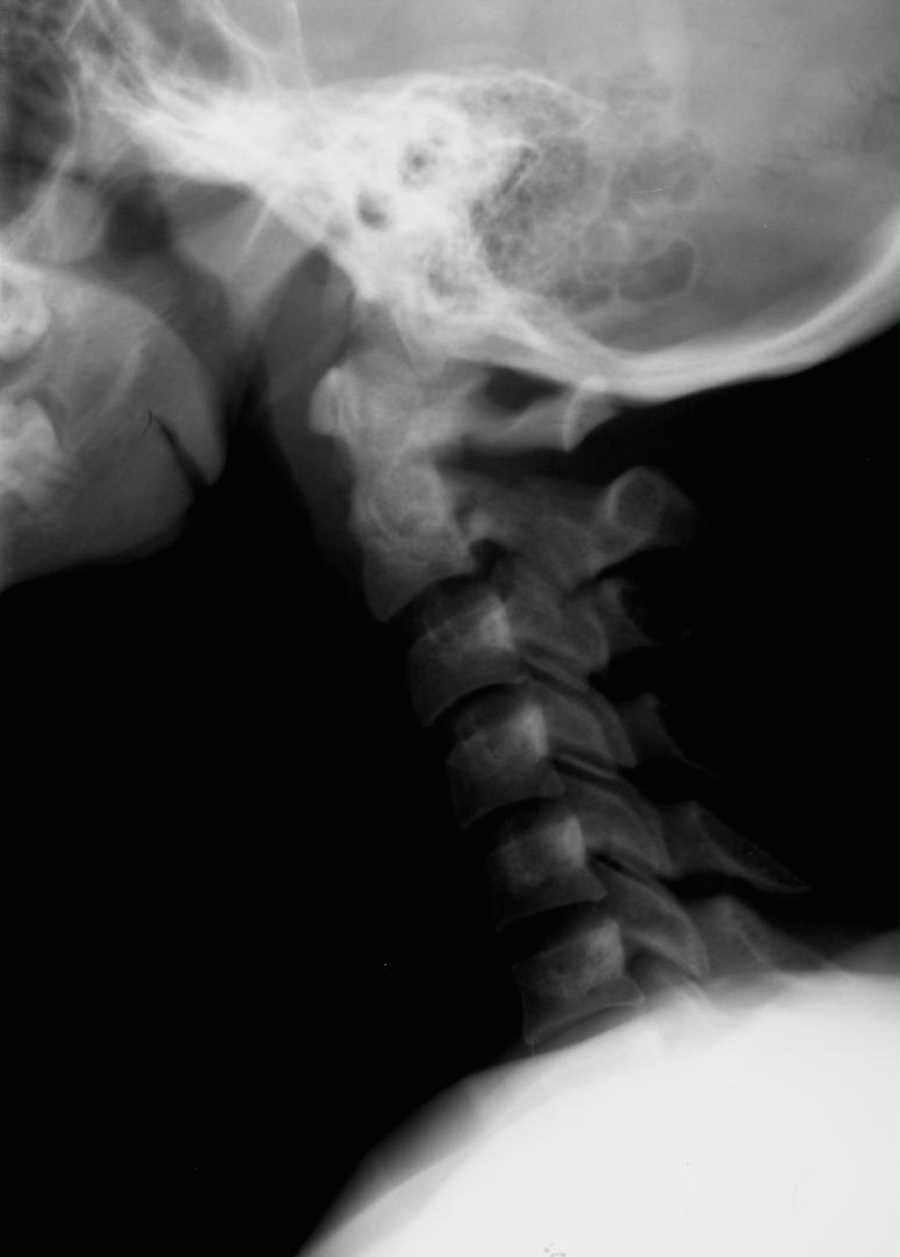

Hangman's Fracture X Ray . Typical features of a hangman's fracture with associated ligamentous injuries. Traumatic spondylolisthesis of axis, also known as a hangman's fracture, is a traumatic fracture of the bilateral pars interarticularis of c2. Learn about the clinical presentation, imaging findings, and classification of hangman’s fracture, a type of cervical spine injury caused by. A hangman’s fracture is a bilateral fracture traversing the pars interarticularis of cervical vertebrae 2 (c2) with an associated traumatic subluxation of c2 on cervical vertebrae 3 (c3). When hangman’s fracture is a result of major trauma, it is usually found as part of a patient’s evaluation in the emergency department.

Xray of the cervical spine showing Hangman's fracture with significant Hangman's Fracture X Ray Traumatic spondylolisthesis of axis, also known as a hangman's fracture, is a traumatic fracture of the bilateral pars interarticularis of c2. Learn about the clinical presentation, imaging findings, and classification of hangman’s fracture, a type of cervical spine injury caused by. A hangman’s fracture is a bilateral fracture traversing the pars interarticularis of cervical vertebrae 2 (c2) with an associated. Hangman's Fracture X Ray.